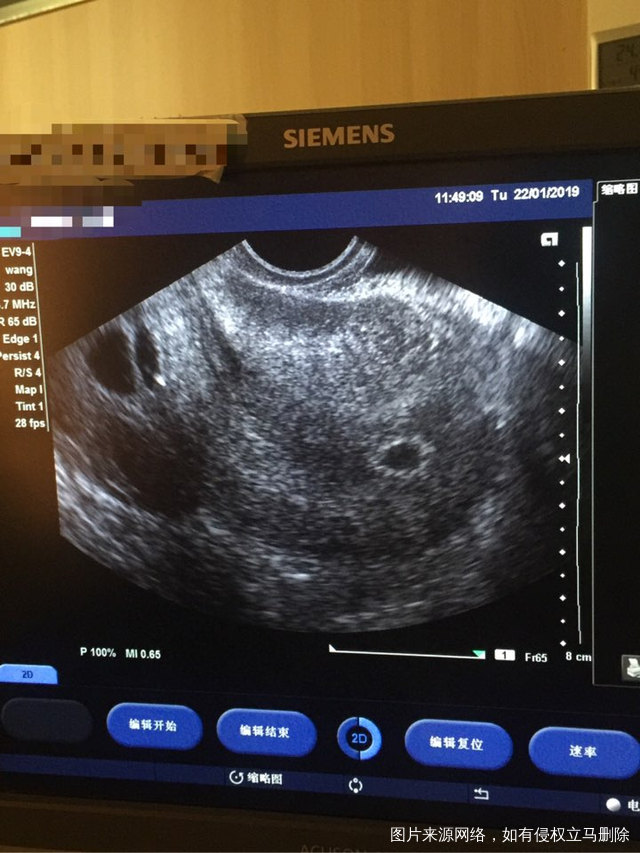

这种必须做手术么还是取了胚胎不是非要做

这个手术不是非得要马上做,需要根据你的年龄、生育计划等来综合评估并权衡利弊后再决定是否需要手术以及什么时候做。如果是做试管通常为了避免输卵管积液及炎症因子逆流至宫腔影响胚胎着床等,会行输卵管结扎等手术,这个手术通常在移植前完成